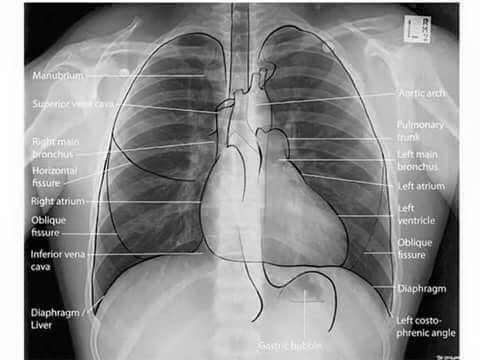

SISTEMÁTICA DE OBSERVACIÓN: DE AFUERA HACIA ADENTRO

Pasos para describir la radiografía de tórax:

Partes blandas torácicas y extratorácicas: Cuello, axilar, hombros, mamas ya abdomen superior.

Estructuras óseas: Vértebras, costillas. Se observa si hay fracturas, huesos supernumerarios, imágenes osteoríticas (masa), etc…

Cúpula (senos) diafragmáticas: El seno diafragmático derecho esté (2 – 3 cm más alto) que el izquierdo, su morfología, si sus ángulos son costodiafragmáticos (si está pegado a las costillas) o cardiofrénicos (si está pegado al corazón), si hay acumulación de líquidos etc…

Mediastino: Ensanchamientos, tiene timo (niños)

Silueta cardiaca: Se observa su tamaño y morfología, si hay alteración a nivel retrocardíaco

Claridad traquebronquial: Posición, calibre y su ángulo carinal

Playas pulmonares: Es el parénquima pulmonar